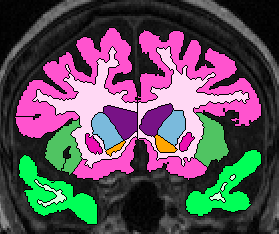

| Temporal Lobe White Matter: Anteriorly, simply relabel the cerebral white matter in the temporal lobe as temporal lobe white matter (fig 2). When the white matter becomes continuous from the temporal lobe to the frontal, draw a horizontal line laterally from the inferior Insula, then extract the temporal white matter, leaving it unlabeled for the time being (fig 3- this image show it labeled, however). Once the frontal lobe gray matter superior to the amygdala is gone, draw a straight horizontal line from one fronto-temporal junction (lateral sulcus) to the other and extract the temporal white matter (fig 4).

When parietal lobe shows up ventrally, draw a line from the medial parietal-temporal junction to the the lateral one(fig 5).